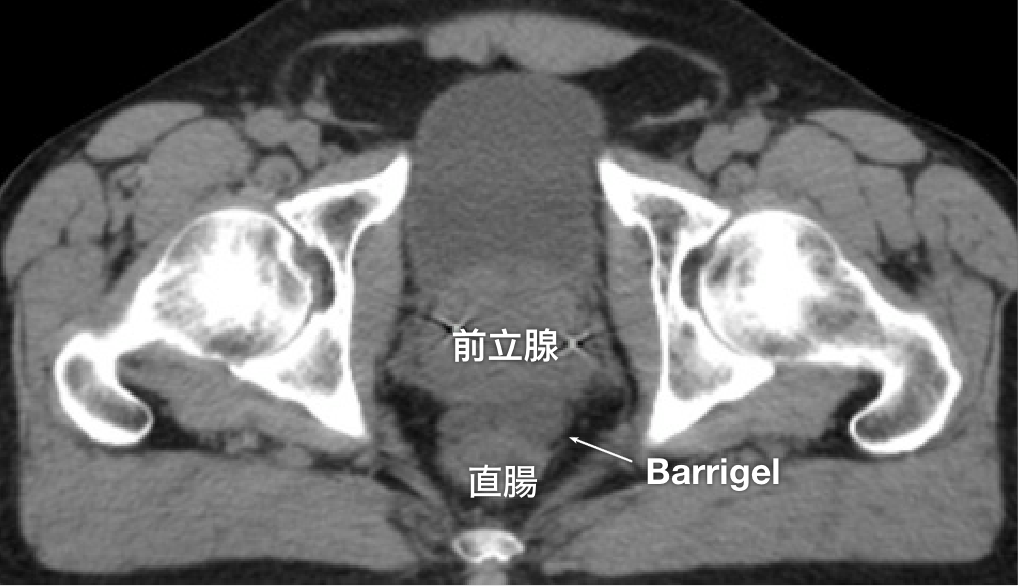

CT画像

CT画像提供:Glen Gejerman, MD

Radiation Oncologist; New Jersey, United States